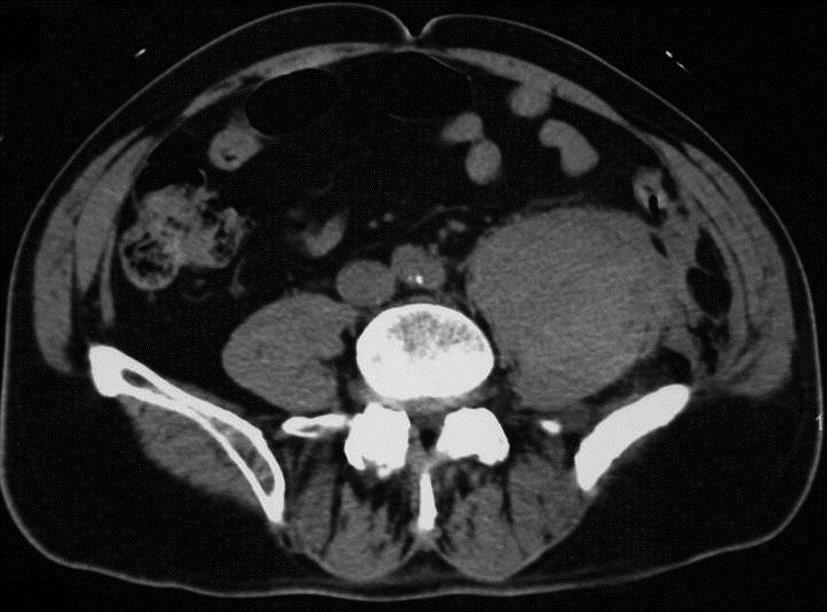

La tamponnade peut provoquer une dyspnée avec désaturation avec auscultation normale (en dehors de la tachycardie), le frottement péricardique étant assez inconstant et plus volontiers présent en cas d’épanchement de faible abondance.